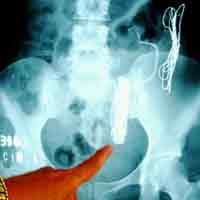

Pensiun Makan Logam Setelah Tersedak Pedal Sepeda

Pria ini sudah mengonsumsi 25.000 bola lampu, 12.000 garpu, 2.000 sendok, 2.600 piring dan hampir 6.000 piringan hitam vinil. Tapi di usia 80 tahun ia pensiun makan logam karena hampir meninggal setelah tersedak pedal sepeda.